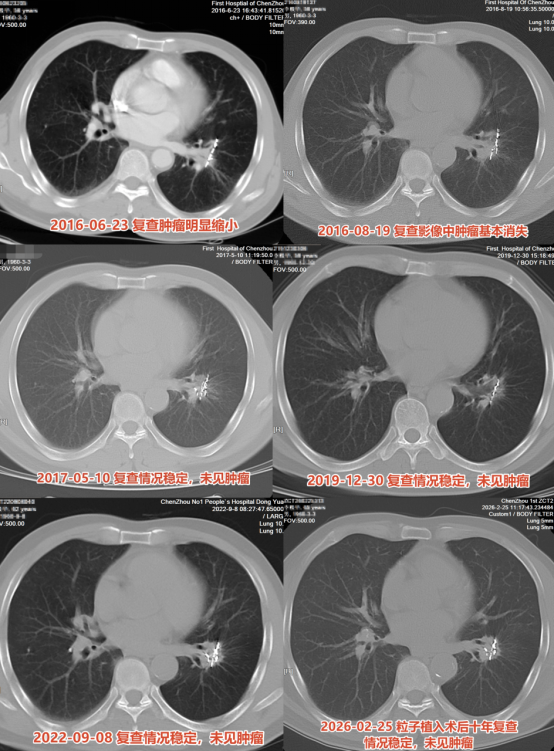

手术后,联合三个疗程化疗的全身治疗随即展开——局部精准控制与全身清扫同步进行。2016年8月19日,术后不到三个月,复查CT结果显示原本边界不清、占据左肺下叶的肿块几乎消失殆尽,以及那些已失去放射活性、静静留存的金属粒子。医学上,这被称为临床完全缓解。此后,李伯伯每隔几年随访复查CT,影像持续保持干净、无进展的状态。直到2026年的今天,再次复查显示术后十年,没有复发,没有进展。